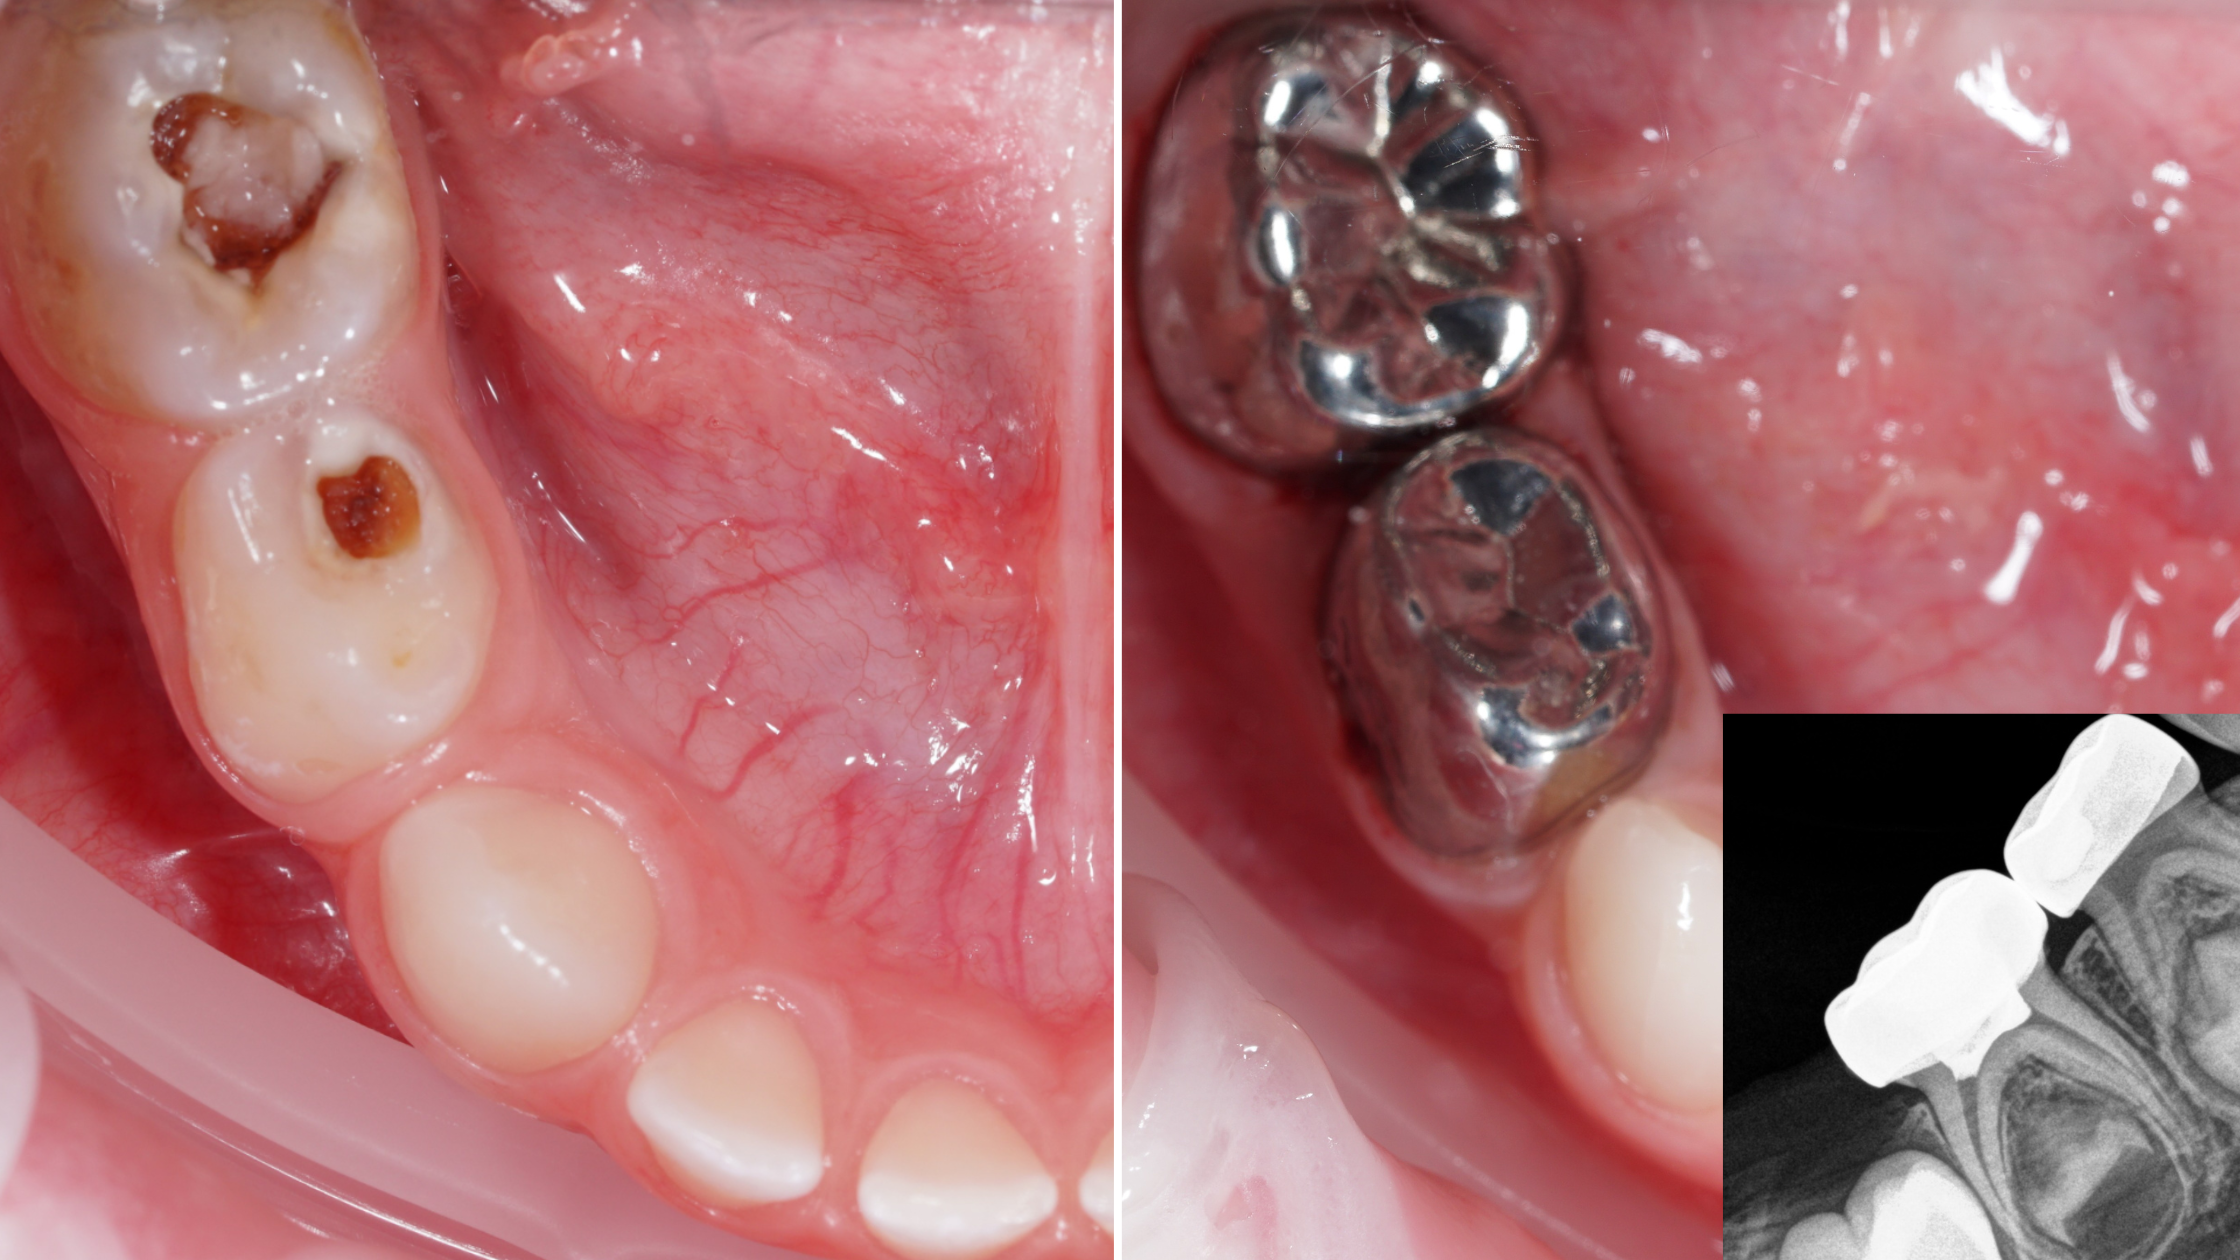

Podczas kursu przekażemy Ci jasne, oparte na EBD wytyczne dotyczące postępowania w najczęstszych sytuacjach klinicznych spotykanych w gabinecie stomatologii dziecięcej. Zaczniemy od diagnostyki i planowania leczenia, które pozwolą właściwie określić problem pacjenta i zaplanować cały proces terapeutyczny. Następnie przejdziemy przez szczegółowe algorytmy postępowania w najpowszechniejszych schorzeniach - zapaleniach miazgi, ekstrakcjach, odbudowie ubytków, pracy z koronami stalowymi. Omawiamy je na podstawie realnych przypadków klinicznych, co ułatwia zrozumienie procedur i przeniesienie ich do własnej praktyki.

• analiza przypadków i zdjęć RVG: wskazania, przebieg, efekty leczenia

Korony stalowe (SSC) - wprowadzenie: podstawowa wiedza i umiejętności kliniczne

• wskazania do zastosowania koron stalowych w zębach mlecznych

• dobór rozmiaru i technika dopasowania

• etapy preparacji i cementowania - bezpieczny i przewidywalny protokół

• typowe błędy i ich korekta

• SSC jako metoda przywracania funkcji i trwałości zęba mlecznego

Szlifowanie zębów mlecznych pod korony

• założenie korony stalowej - technika Hall

• szlifowanie 2-3 zębów mlecznych pod korony stalowe

• dobór rozmiaru korony, przymiarka

• cementowanie koron stalowych